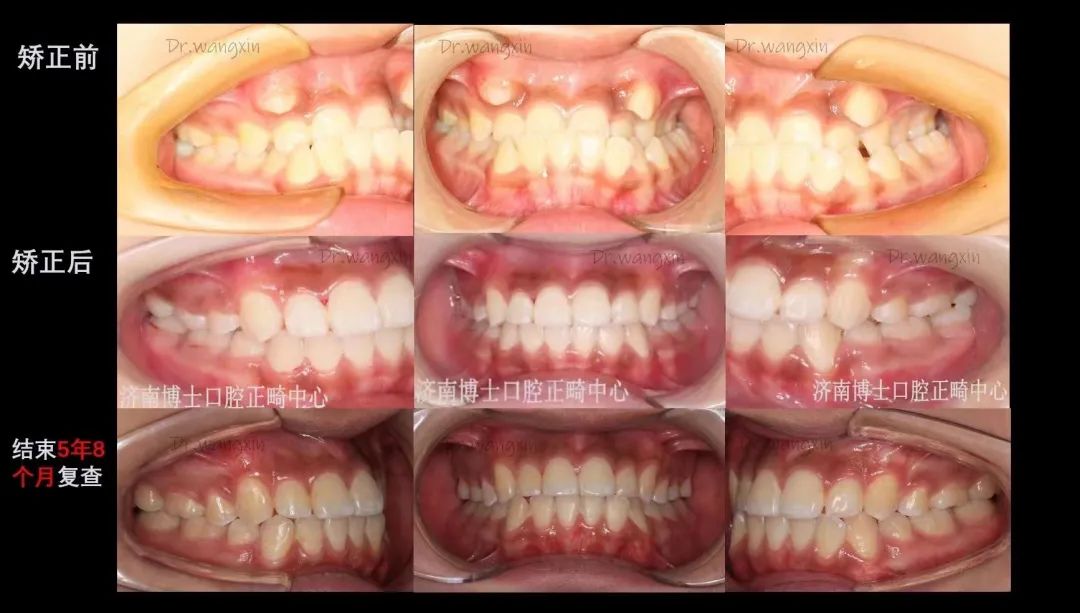

王新,口腔医学硕士,山东省首批隐适美认证医师、隐适美青年讲师;时代天使认证讲师;2008年起跟随张士杰教授从事口腔正畸工作,并成立博士口腔数字化正畸诊疗中心,负责医护团队的带教培训和管理工作。擅长:儿童错颌畸形的预防矫治及阻断矫治,青少年及成人各类错合畸形的矫治(固定矫正、隐形矫治、舌侧矫治)、严重骨性错颌畸形的正畸-正颌手术治疗、错颌畸形伴有牙周病、缺失牙等复杂病例的多学科联合治疗等。